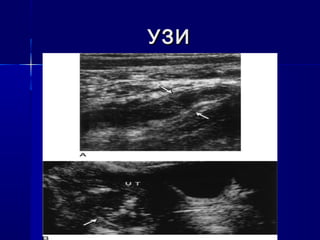

 УЗИУЗИ

УЗИУЗИ